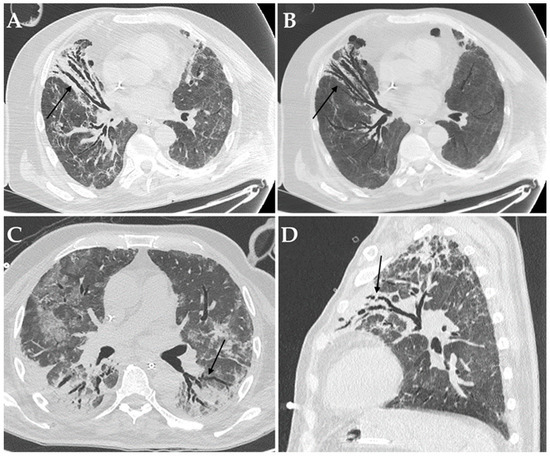

Figure 4.

Axial HRCT images of a patient with COVID-19 ARDS admitted to ICU with bronchiectasis in the middle lobe (black arrow in (A)), being more evident at Minimum Intensity Projection (MIP) reconstruction (black arrow in (B)); Aspergillus niger was later detected in the bronchoalveolar lavage of the patient. Axial HRCT image of a different patient with COVID-19 ARDS with superinfection by Klebsiella pneumoniae and bronchiectasis in the dorsal segment of the left upper lobe (black arrow in (C)). Sagittal HRCT image of a different patient with COVID-19 ARDS showing bronchiectasis in the left upper lobe (black arrow in (D)) and presenting with elevated serum-galactomannan levels compatible with Aspergillus spp. superinfection.